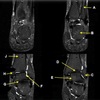

5

Perfectly

12

Q

What is letter B?

A

BICEPS TENDON (LONG HEAD)

How well did you know this?

1

Not at all

2